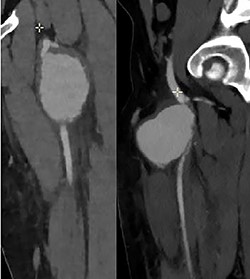

Ultrasonography (US) of the left thigh showed an aneurysmal dilatation of the SFA measuring 67 × 50 × 80 mm (Fig. 2) on the anterior aspect of the proximal third of the thigh. Computer tomography angiogram (CTA) confirmed a 64 × 80 × 87-mm PSA developed on the anterior side of the proximal left SFA (Fig. 3). The other arterial axes were healthy and normal. Supplementary imaging examinations did not identify any additional aneurysms.

Computer tomography angiogram showed a PSA of the proximal SFA.